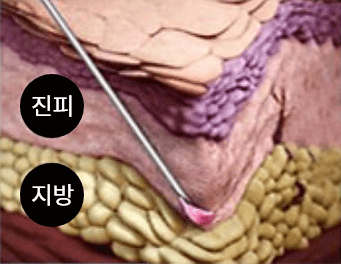

쥬베룩 시술원리

PRINCIPLE OF JUVELOOK자가 콜라겐 생성으로 자연스러운 볼륨 효과

-

볼륨이 꺼진 부위와 주름이

있는 부위의 진피와 지방조직

사이에 쥬베룩을 주입 -